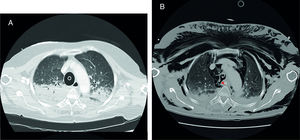

Mujer de 70 años sin antecedentes de interés traída al hospital tras 35min de RCP avanzada que incluye intubación orotraqueal (técnica no descrita en el informe) y uso de dispositivo de compresión torácica mecánica. En urgencias se realiza TC torácico (A) en el que informan de intubación selectiva del bronquio principal derecho. A su llegada a la UCI, se retira el tubo endotraqueal, con aparición inmediata de extenso enfisema subcutáneo. Se repite TC torácico (B) en el que se aprecia solución de continuidad en la pared posterolateral derecha de la tráquea en relación a rotura traqueal, condicionando neumotórax apical bilateral, extenso neumomediastino y enfisema subcutáneo (fig. 1). A los 3 días de ingreso en la unidad, la paciente fallece tras LTSV por encefalopatía anóxica grave.